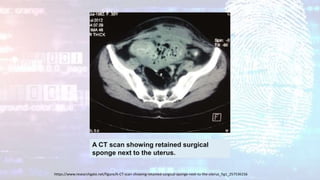

A CT scan showing retained surgical

sponge next to the uterus.

https://www.researchgate.net/figure/A-CT-scan-showing-retained-surgical-sponge-next-to-the-uterus_fig1_257536156

A CT scanshowing retained surgical sponge next to the uterus. https://www.researchgate.net/figure/A-CT-scan-showing-retained-surgical-sponge-next-to-the-uterus_fig1_257536156